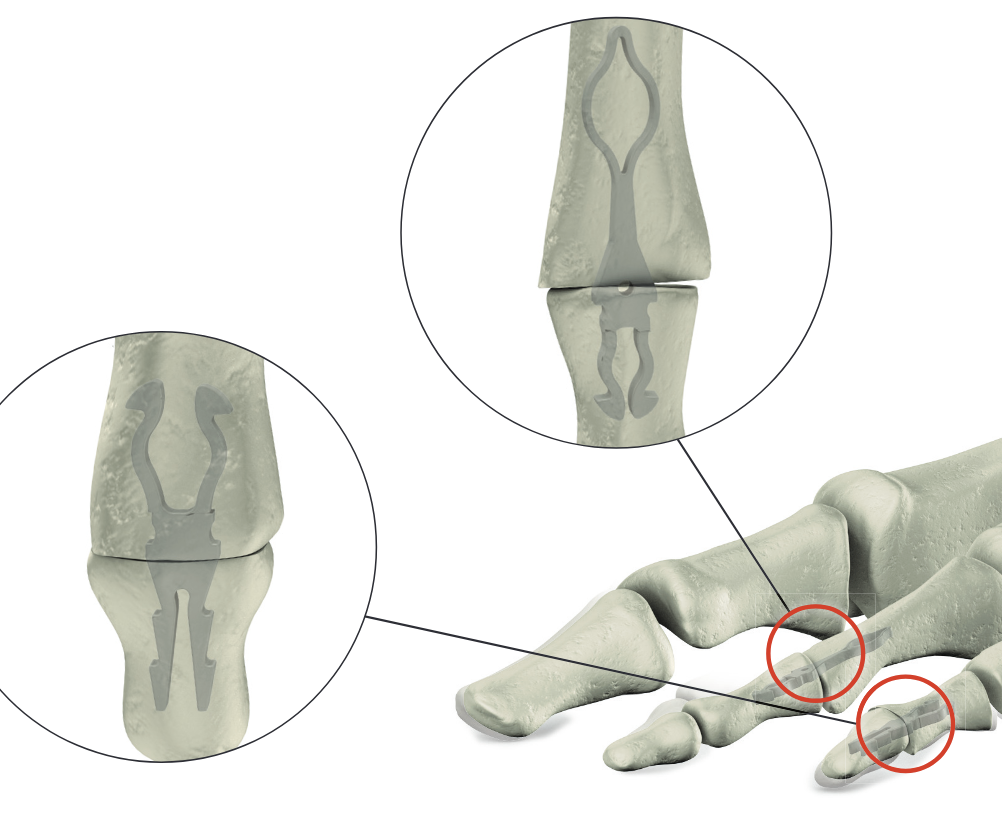

+/- intramedullary device

Stryker SmartToe IM device ToeGrip

- PIPJ fusions

- 3000 K wires, 350 SmartToe, 200 ToeGrip

- highest union rate with SmartToe

- highest failure rate with SmartToe